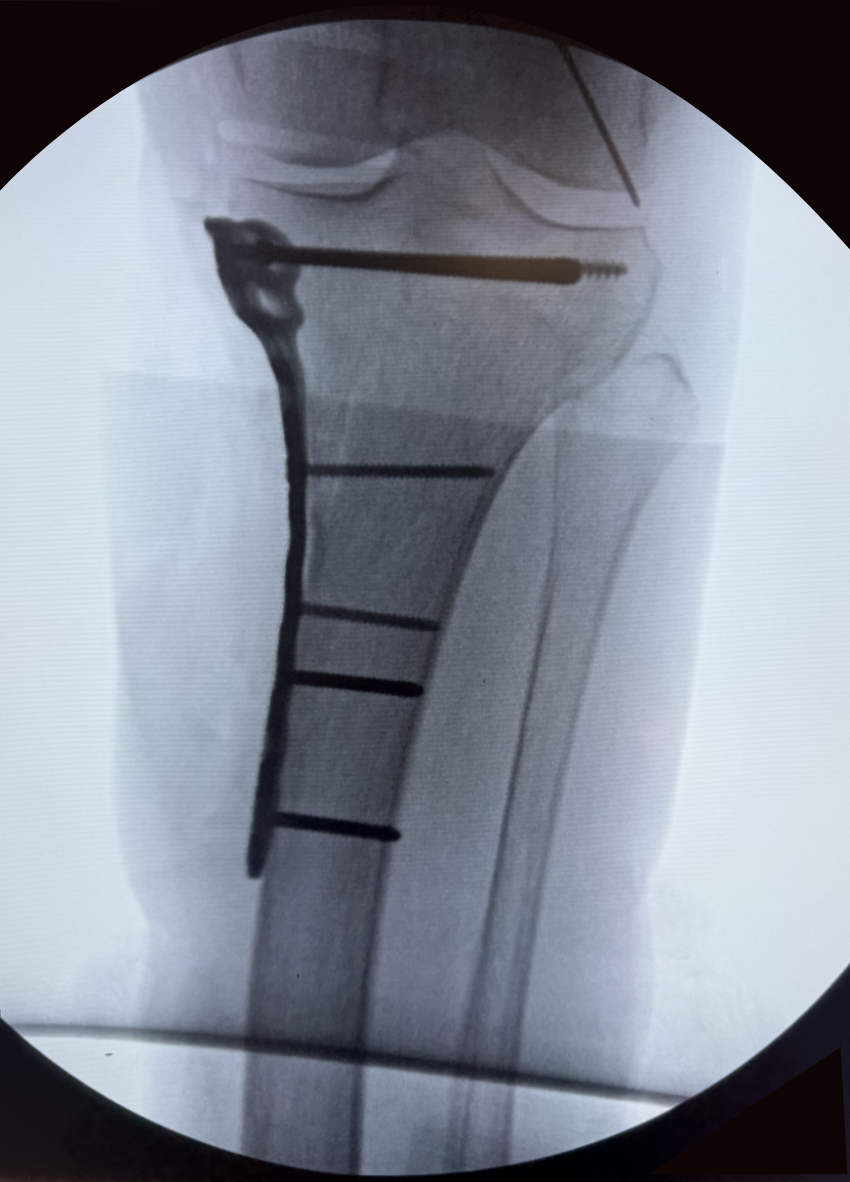

Internal and External Fixation Techniques

Internal Fixation:

This involves using specialized implants like plates, screws, rods (intramedullary nails), or wires to stabilize the broken bone fragments from within. These devices hold the bone in proper alignment while it heals.

Knee Fracture

Complex Fracture Reconstruction and Non-Union Treatment

Some fractures are particularly challenging, such as those involving multiple fragments, significant bone loss, or those that fail to heal (non-unions). Dr. Arroyo has extensive experience in complex fracture reconstruction, utilizing advanced techniques like bone grafting, specialized plating systems, and biologic agents to salvage limbs and restore function in even the most difficult cases.

Hip fracture with 3 screws.